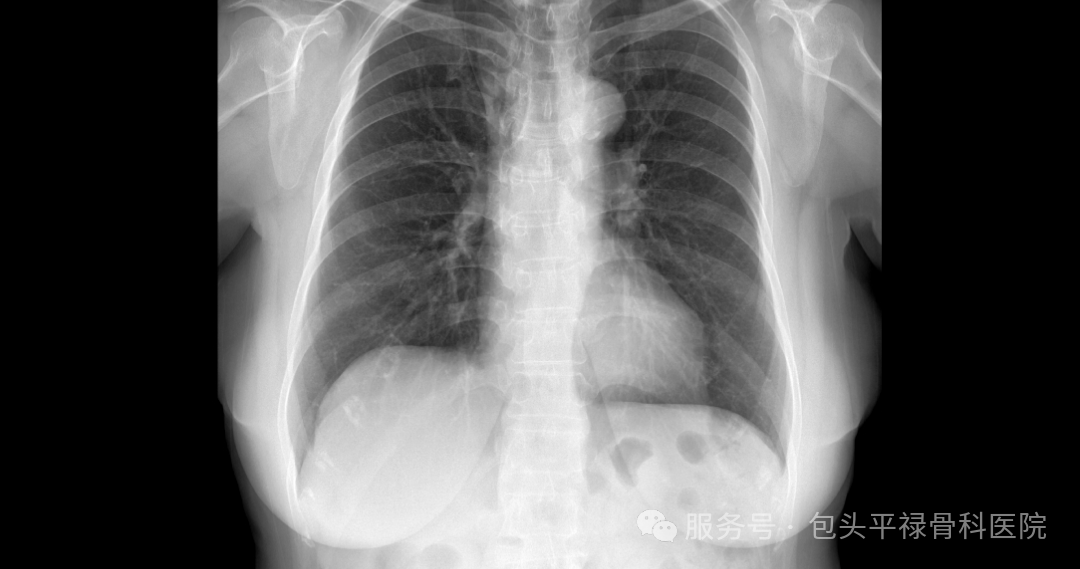

DR-CT-MRI影像对比

图源:包头平禄骨科医院

DR,即数字X射线成像,它利用X射线的穿透能力成像,X线会穿过人体在底片上留下黑白色影像,当它遇到被遮挡的部位(如骨骼)时无法穿透,在底片上显示为白色,反之,则显示为黑色。

胸部:检查肋骨是否骨折,脊柱是否侧弯、骨折;判断肺部是否有炎症、肿瘤、结核、胸腔积液、气胸等情况。